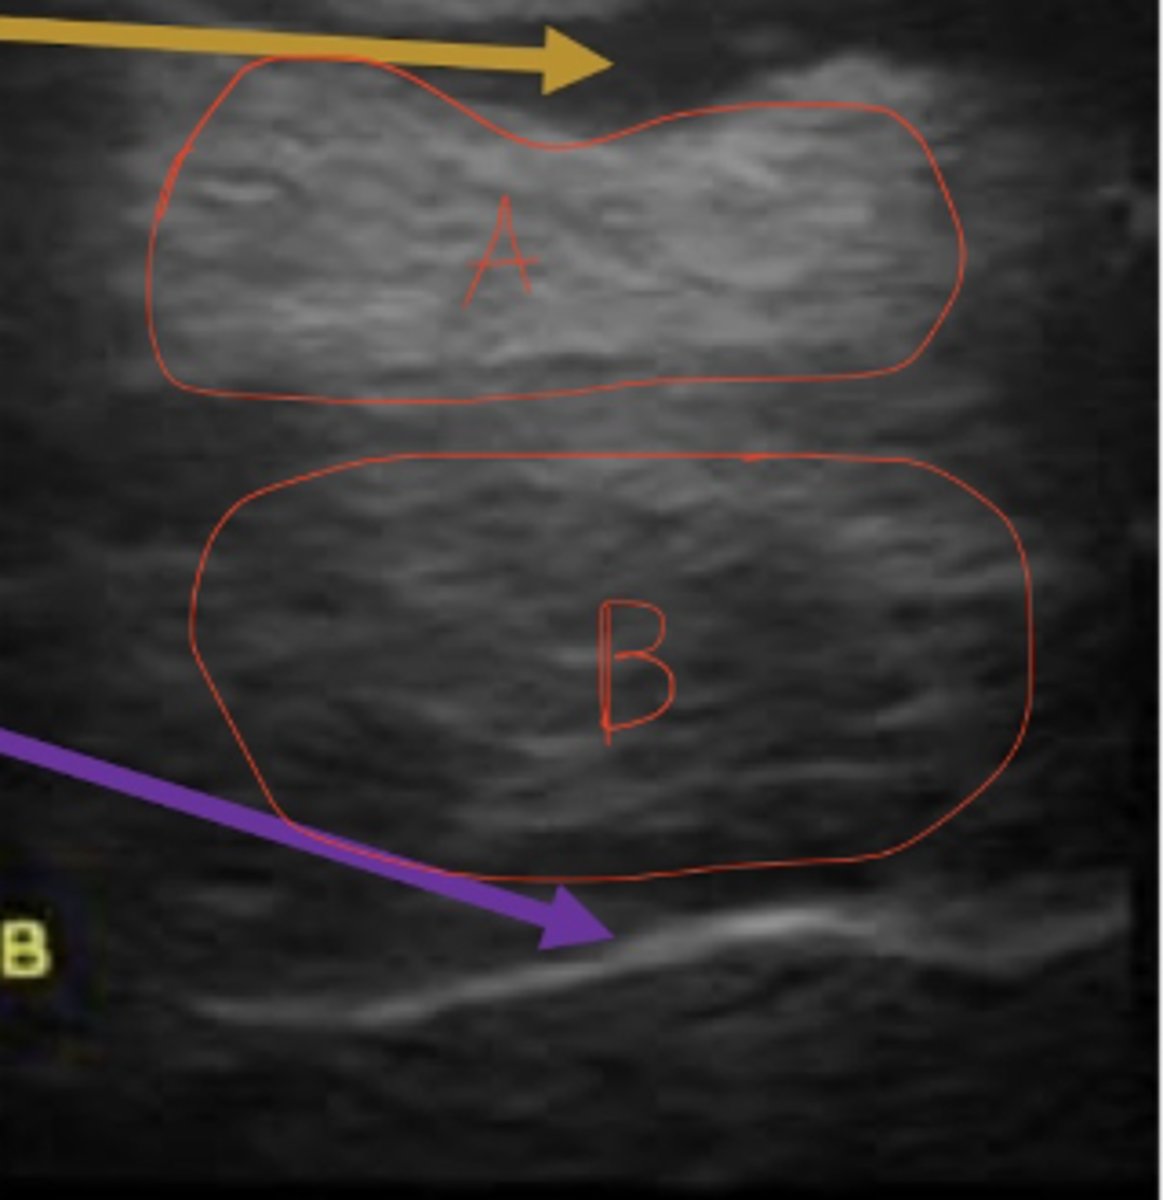

A is hyperechoic compared to B

How does A relate to B in echogenicity?

7 year old thoroughbred presents with acute lameness, swelling of metacarpal?; ultrasound shows this- what is this?